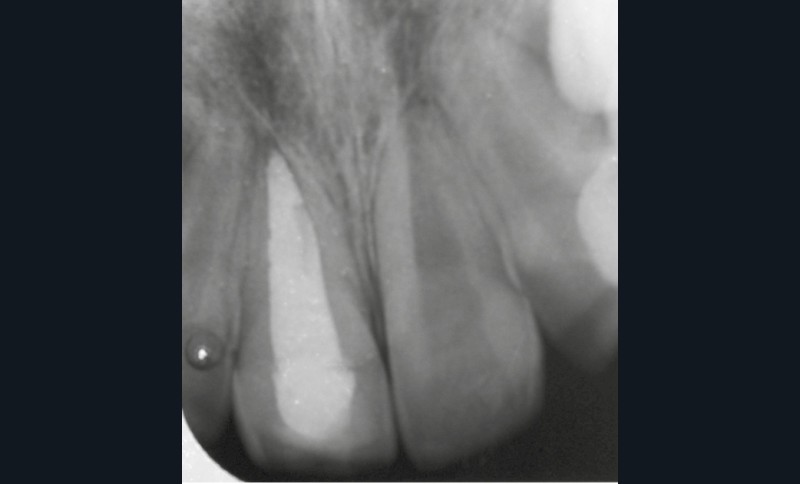

Enfant de 9 ans dont une incisive centrale maxillaire a été expulsée en jouant au football. Appel immédiat de la mère à qui l’on conseille de conserver la dent expulsée dans du sérum physiologique (fig. 1). Le temps extra-alvéolaire à sec a été inférieur à 5 minutes. Le patient arrive 40 minutes après le traumatisme dans l’Unité d’Odontologie pédiatrique. Après interrogatoire, examen clinique et radiographique, un rinçage de l’alvéole est effectué et la dent est réimplantée le plus rapidement possible (fig. 2). Une contention semi-rigide est ensuite placée (fig. 2). La dent étant mature, la prise en charge endodontique (séance de Ca(OH)2 puis obturation à la gutta percha) débute deux semaines plus tard (fig. 3 et 4) afin de limiter les risques d’infection, de résorption. Le suivi sur quatre années montre une dent fonctionnelle, sans ankylose ni résorption radiculaire ou osseuse.